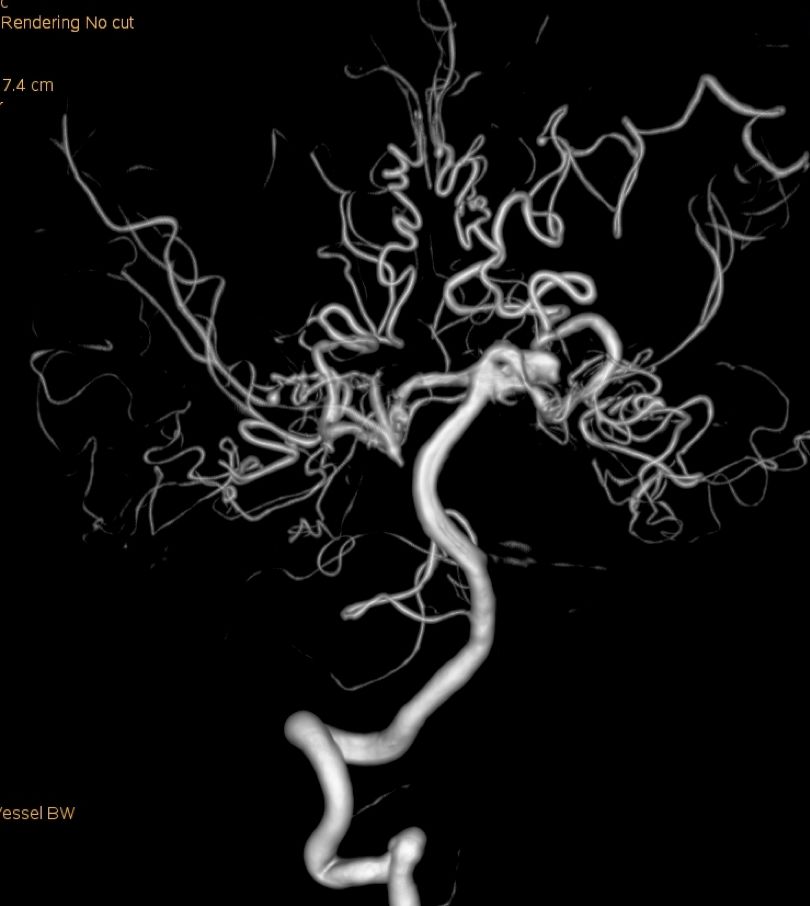

本次术前DSA(图3)

图3

颅内多发动脉瘤(左侧小脑上动脉)

蛛网膜下腔出血

烟雾病

左侧大脑后动脉狭窄